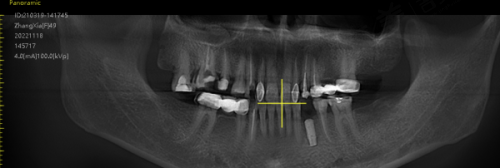

特色项目 - 老年全口种植项目:该项目的独特之处在于,医生团队会在术前对老年患者进行全方面的口腔检查和身体评估,包括口腔CT扫描、血常规、凝血功能等检查,以确保患者身体状况适合种植手术。在种植过程中,采用精良的种植技术和高品质的种植体,能够有效缩短种植周期,提高种植成功几率。而且术后还会为患者提供专精的护理指导,帮助患者尽快修复。